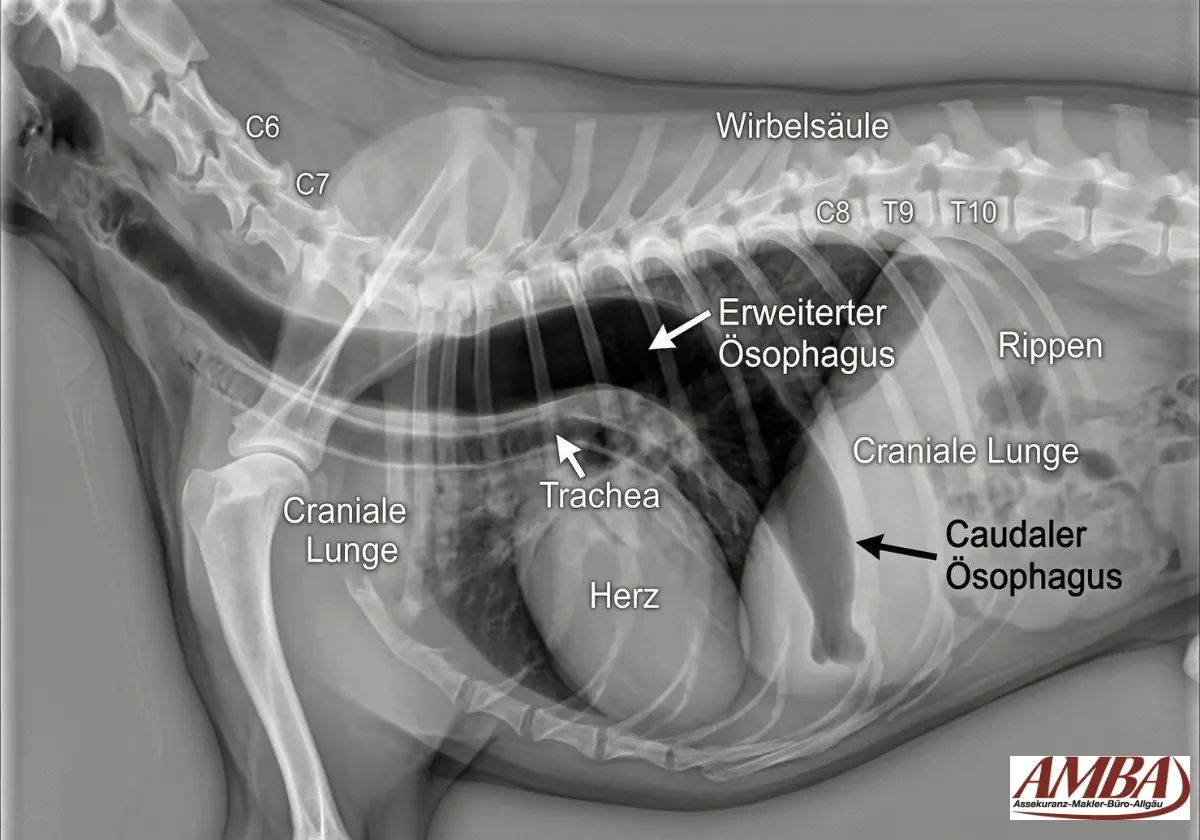

Die Diagnose wird in der Regel mit Thorax-Röntgen gestellt.

Auf den Aufnahmen sieht man oft eine mit Luft, Flüssigkeit oder Futter erweiterte Speiseröhre; gleichzeitig lässt sich prüfen, ob bereits Hinweise auf eine Aspirationspneumonie bestehen. Bei vielen Hunden ist das Röntgen der entscheidende erste Schritt, weil es schnell verfügbar ist und die typische Erweiterung gut zeigt.